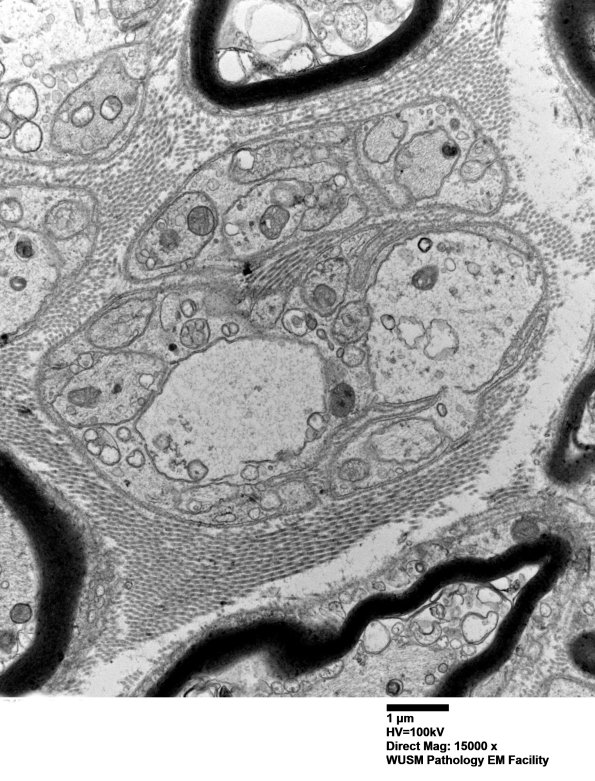

These structures are surrounded by Schwann cell cytoplasm but seem to be held with other smaller axons in what appears to be a developing Remak bundle; however, they appear too large. (electron micrograph)